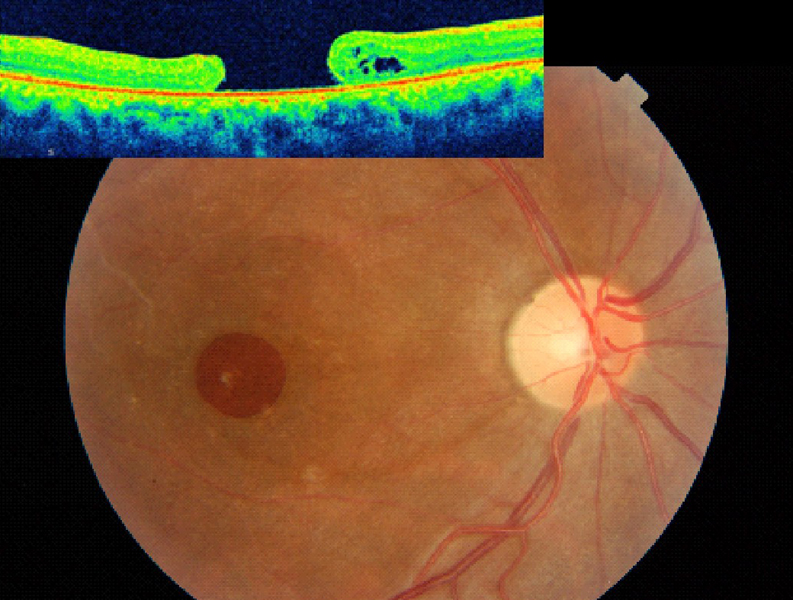

El valor pronóstico está determinado en la uveítis por el tipo de uveítis, la edad del paciente y el tipo de tratamiento, y también por rasgos característicos obtenidos mediante OCT, como son el grosor retiniano, el patrón del edema macular, la integridad de la capa de unión de los segmentos externos e internos de los fotorreceptores y el estado de la interfase vítreo-mácula. De esta forma, es de gran utilidad a la hora de monitorizar a los pacientes y valorar la respuesta terapéutica (

Figura 3).

Figura 3. Paciente que presenta en su ojo izquierdo edema macular quístico y desprendimiento de retina seroso subfoveal asociado a uveítis posterior por Brucella. Mediante la OCT se monitoriza la respuesta al tratamiento con un implante intravítreo de Ozurdex, observándose como disminuye el grosor retiniano a medida que se reabsorbe el fluido y se normaliza el perfil foveal tras el tratamiento.